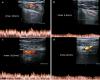

Fig. 7

B-Mode US: longitudinal sub-xiphoid scan of the abdominal aorta performed in supine decubitus. a Measurement of the aorto-mesenteric angle "A" in patient with NCS. Abdominal aorta (short arrow). Superior mesenteric artery (long arrow). b Duplex Doppler US shows a peak speed reduction in left renal vein. c Measurement of the left renal vein diameter. d Power Doppler US shows varicosity of the gonadal plexus (vein diameter 5.5 mm)